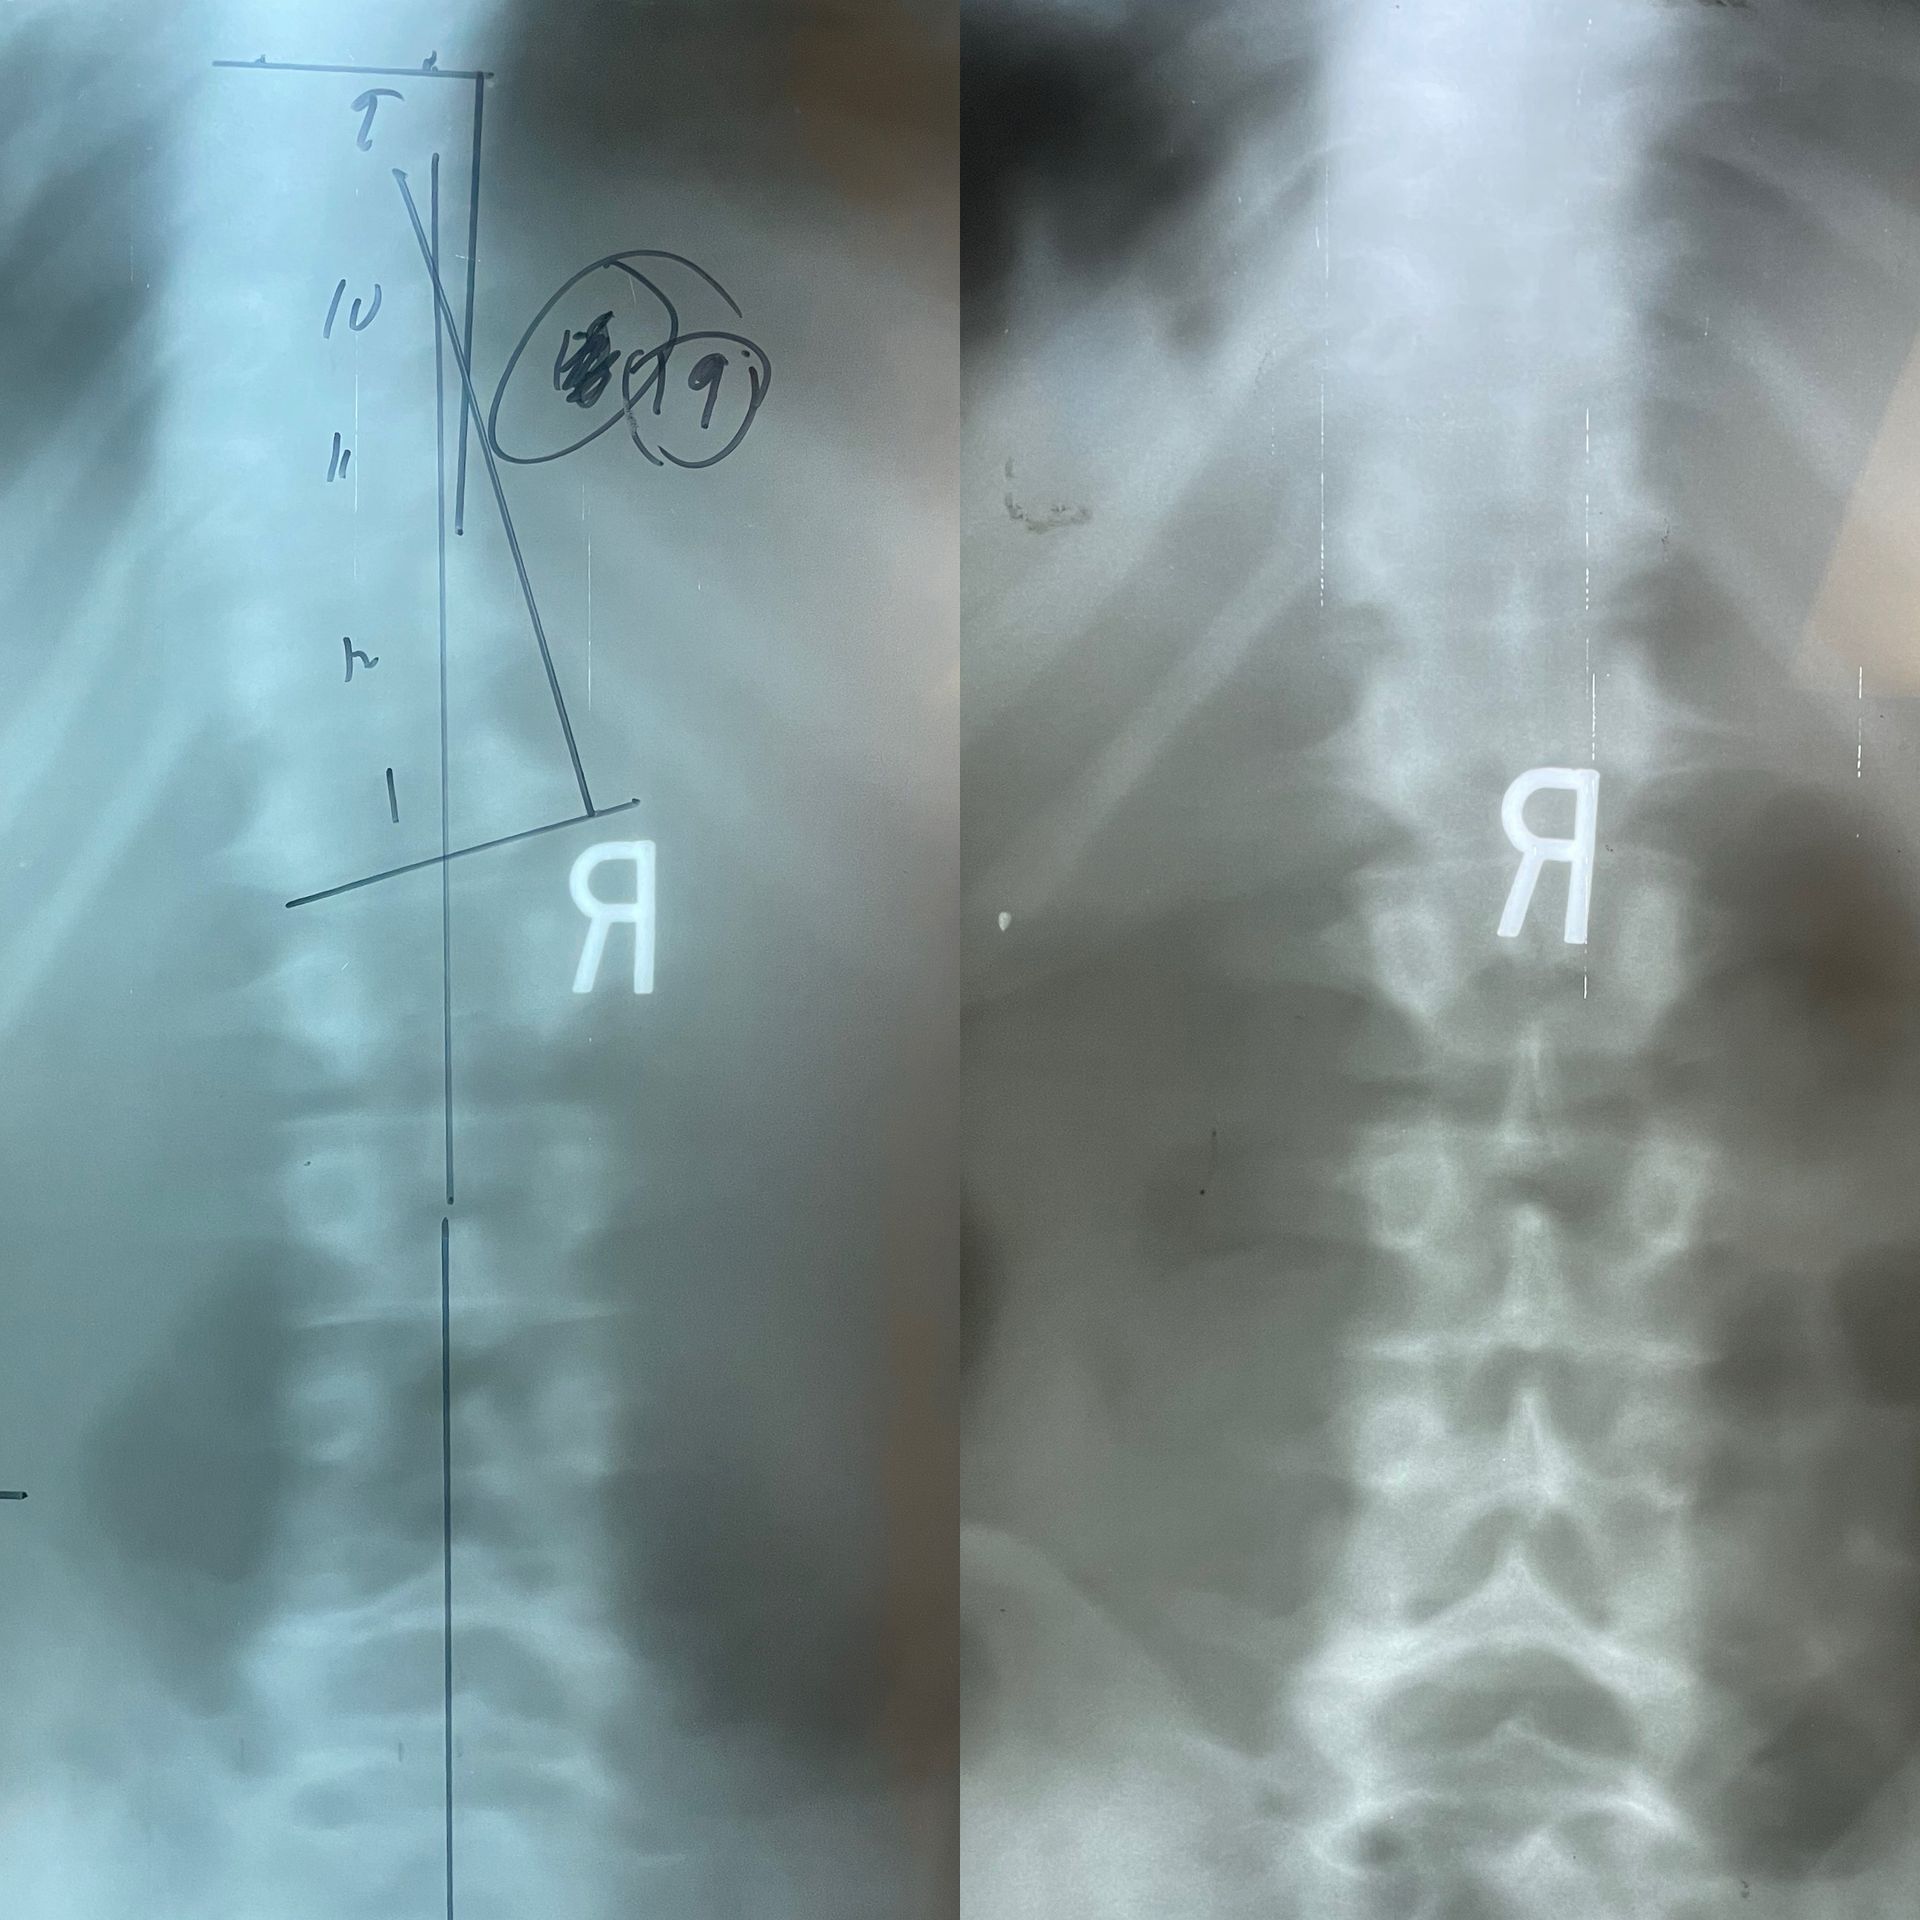

Before

11 year old with rapidly progressing 26 degree curve (all 26 degrees came within 6 months) and spine collapsing to right.

After

After 3 months of scoliosis treatment, spine is at 15 degrees and is more upright.

Before:

27 degree progressing scoliosis

After:

5 months later, 17 degrees